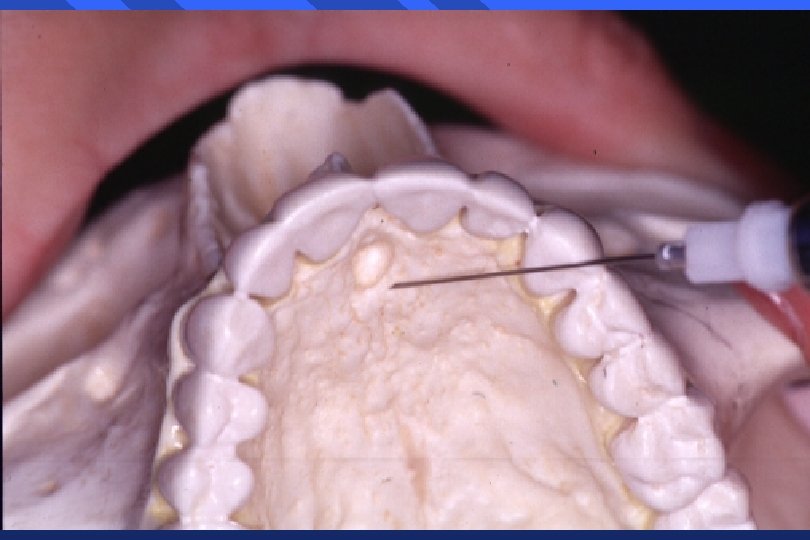

What Is A Palatal Block . the porous palatal tissue and bone allow penetration of the anesthetic to the dental plexus of the asa and msa nerves (on one side), which provide innervation to pulps of the premolars through incisors and, sometimes, the mesiobuccal root of the first permanent molar. The primary method is infiltration anaesthesia. As the name suggests it blocks the anterior palatine. This chapter will describe the infiltration and regional block methods used in the upper jaw. The greater palatine nerve provides. the nasopalatine nerve block, otherwise known as the incisive nerve block or sphenopalatine nerve block, anesthetizes the nasopalatine nerves bilaterally. This technique is indicated when treatment requires anesthesia of the lingual aspect of multiple. when the psa block is combined with the anterior superior alveolar (asa) block using an infraorbital approach,. this chapter on pulpal anesthetic methods for the upper arch (maxillary) teeth addresses the following procedures. Used to block the anterior palatine nerve. a nasopalatine nerve block anesthetizes the palatal tissues of the 6 maxillary anterior teeth. In this technique, the anesthetic solution is deposited in the area of the incisive foramen. However, many dentists lack confidence with respect to administering the maxillary block, as they are relatively unfamiliar with the anatomy of the region as it relates to this method. anterior or greater palatine nerve block:

However, many dentists lack confidence with respect to administering the maxillary block, as they are relatively unfamiliar with the anatomy of the region as it relates to this method. In this technique, the anesthetic solution is deposited in the area of the incisive foramen. This technique is indicated when treatment requires anesthesia of the lingual aspect of multiple. Used to block the anterior palatine nerve. The primary method is infiltration anaesthesia. The greater palatine nerve provides. This chapter will describe the infiltration and regional block methods used in the upper jaw. this chapter on pulpal anesthetic methods for the upper arch (maxillary) teeth addresses the following procedures. the nasopalatine nerve block, otherwise known as the incisive nerve block or sphenopalatine nerve block, anesthetizes the nasopalatine nerves bilaterally. the porous palatal tissue and bone allow penetration of the anesthetic to the dental plexus of the asa and msa nerves (on one side), which provide innervation to pulps of the premolars through incisors and, sometimes, the mesiobuccal root of the first permanent molar.

What Is A Palatal Block However, many dentists lack confidence with respect to administering the maxillary block, as they are relatively unfamiliar with the anatomy of the region as it relates to this method. when the psa block is combined with the anterior superior alveolar (asa) block using an infraorbital approach,. As the name suggests it blocks the anterior palatine. Used to block the anterior palatine nerve. This chapter will describe the infiltration and regional block methods used in the upper jaw. a nasopalatine nerve block anesthetizes the palatal tissues of the 6 maxillary anterior teeth. In this technique, the anesthetic solution is deposited in the area of the incisive foramen. this chapter on pulpal anesthetic methods for the upper arch (maxillary) teeth addresses the following procedures. anterior or greater palatine nerve block: However, many dentists lack confidence with respect to administering the maxillary block, as they are relatively unfamiliar with the anatomy of the region as it relates to this method. The primary method is infiltration anaesthesia. the porous palatal tissue and bone allow penetration of the anesthetic to the dental plexus of the asa and msa nerves (on one side), which provide innervation to pulps of the premolars through incisors and, sometimes, the mesiobuccal root of the first permanent molar. This technique is indicated when treatment requires anesthesia of the lingual aspect of multiple. The greater palatine nerve provides. the nasopalatine nerve block, otherwise known as the incisive nerve block or sphenopalatine nerve block, anesthetizes the nasopalatine nerves bilaterally.